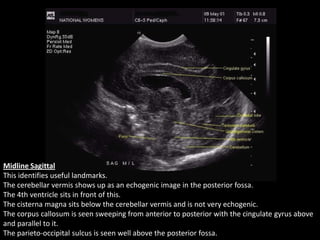

Midline Sagittal

This identifies useful landmarks.

The cerebellar vermis shows up as an echogenic image in the posterior fossa.

The 4th ventricle sits in front of this.

The cisterna magna sits below the cerebellar vermis and is not very echogenic.

The corpus callosum is seen sweeping from anterior to posterior with the cingulate gyrus above

and parallel to it.

The parieto-occipital sulcus is seen well above the posterior fossa.

Midline Sagittal This identifiesuseful landmarks. The cerebellar vermis shows up as an echogenic image in the posterior fossa. The 4th ventricle sits in front of this. The cisterna magna sits below the cerebellar vermis and is not very echogenic. The corpus callosum is seen sweeping from anterior to posterior with the cingulate gyrus above and parallel to it. The parieto-occipital sulcus is seen well above the posterior fossa.